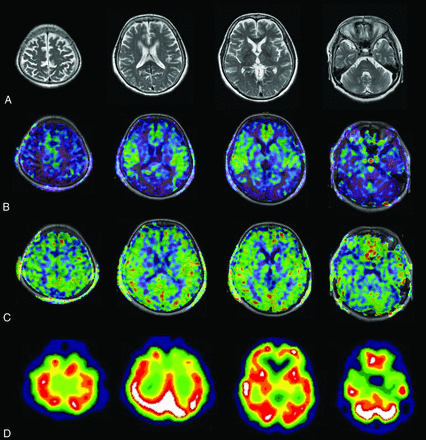

Case 1 was an 86-year-old woman with AD. Her MMSE score was 14. The ASL-MR imaging and SPECT images for this patient are shown in Fig 3. Case 2 was an 83-year-old woman with AD. Her MMSE score was 19. The images for this patient are shown in Fig 4. Case 3 was a 73-year-old woman with MCI due to AD. Her MMSE score was 23. The images for this patient are shown in Fig 5.

An 86-year-old woman with AD. The patient had an MMSE score of 14. Axial images of T2-weighted MR imaging (A), ASL-MR imaging with PLD1.5 in a color-scale fused with T1-weighted MR imaging (B), ASL-MR imaging with PLD2.5 in a color-scale fused with T1-weighted MR imaging (C), and brain perfusion SPECT at the level of the parietal lobe, corona radiata, basal ganglia, and cerebellum (D). Both raters indicated a score of 4 (definitely AD) for PLD1.5 and SPECT and 1 (probably not AD) for PLD2.5.